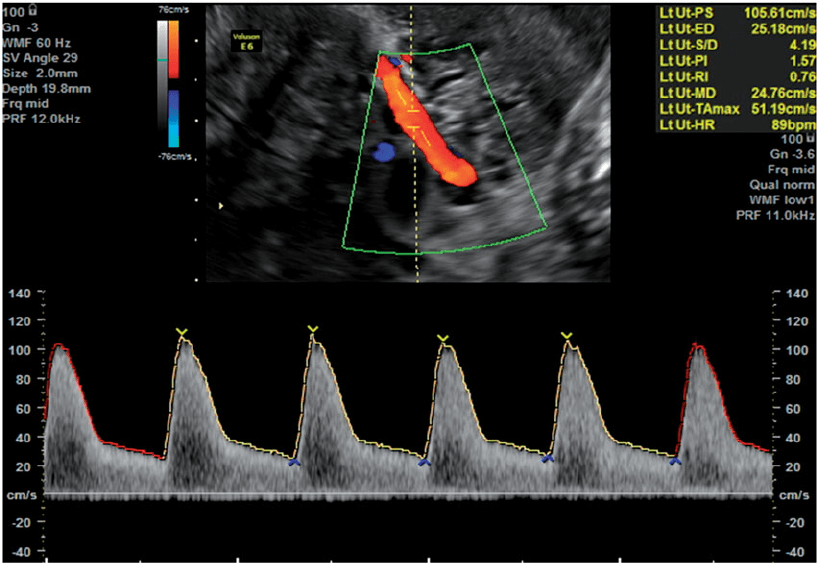

- Uterin Arter Doppler ölçümü.